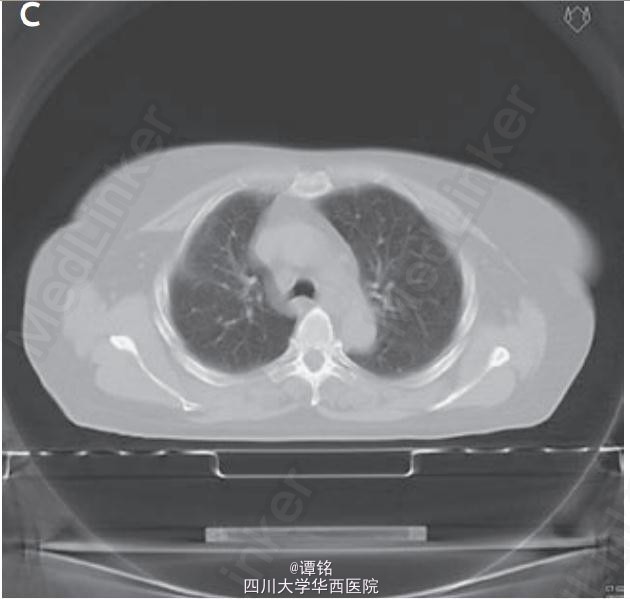

予泼尼松龙100 mg qd,3天后逐渐减量,治疗5周后临床症状消失(图C)